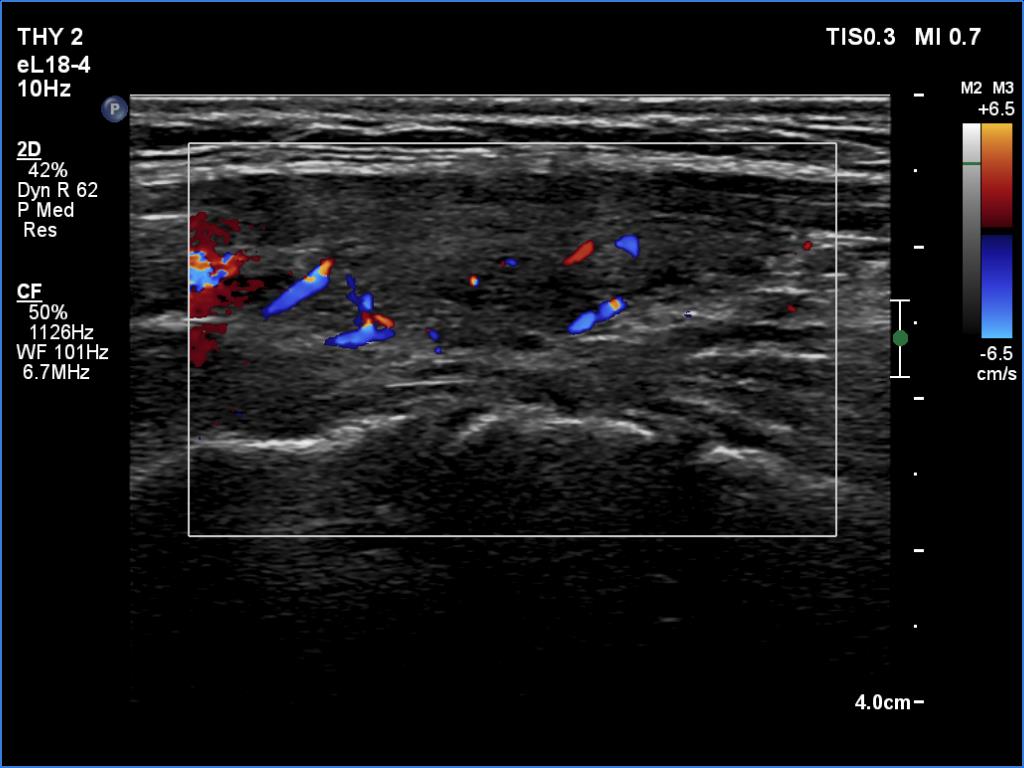

Left lobe, longitudinal view, color Doppler mode. The vascularization is not specific.